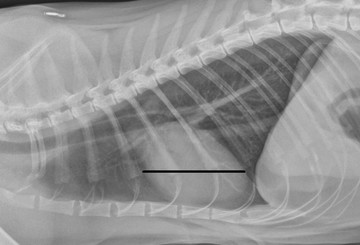

Изобр 2.Количество межреберных пространств, занимаемых сердцем, было оценено в обоих латеральных проекциях в наиболее широкой части горизонтального аспекта силуэта сердца.